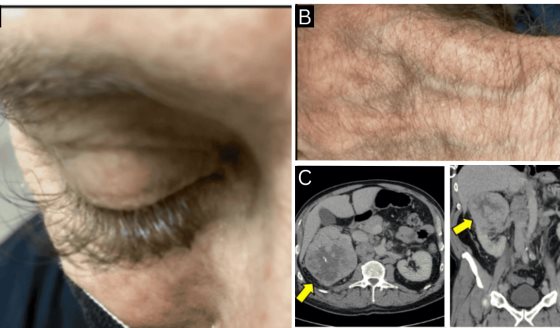

Sífilis primaria: Esta etapa se caracteriza por la aparición de una úlcera indolora, llamada chancro, en el sitio de la infección inicial. Los chancros pueden aparecer en los genitales, el ano, la boca, entre otros lugares. A menudo, esta etapa no produce síntomas notables y puede pasar desapercibida.

Sífilis secundaria: Durante esta etapa, la bacteria Treponema pallidum se disemina por todo el cuerpo a través del torrente sanguíneo, lo que resulta en una erupción cutánea generalizada, fiebre, fatiga y otros síntomas similares a la gripe. También pueden aparecer lesiones mucocutáneas, como condilomas planos, y afectar varios órganos.

Sífilis terciaria: Si la sífilis no se trata, puede progresar a la etapa terciaria, que puede manifestarse de diversas maneras y causar daño grave a órganos como el corazón, el cerebro y los huesos. Esta etapa puede incluir lesiones gomosas en la piel y los órganos internos, así como complicaciones cardiovasculares y neurológicas devastadoras.